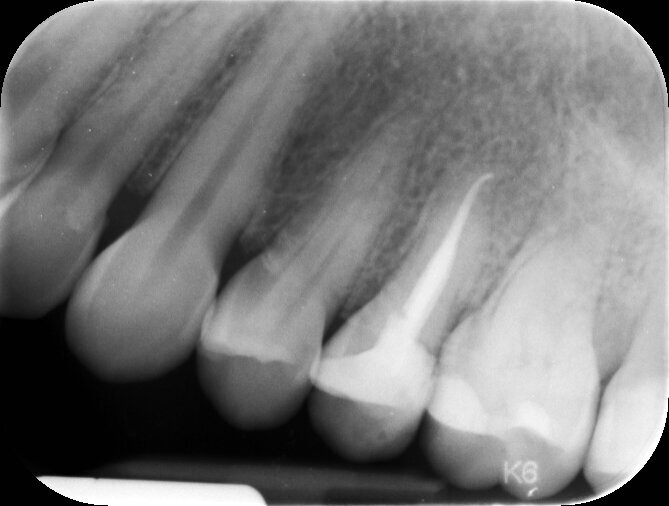

In questo caso dato il mutuo contatto tra osso e impianto non è stato necessario alcun riempimento e seppur altamente stabile, il provvisorio è stato rimosso dal contatto masticatorio e da eventuali svincoli funzionali. Al termine del posizionamento eseguiamo un controllo radiografico che stabilisce il giorno zero d’inserimento, la valutazione globale di posizione e un controllo di eventuali residui cementizi presenti (Fig. 5). Dopo un periodo di consolidamento osseo di 3 mesi si procede al processo di finalizzazione protesica. Il condizionamento dei tessuti molli ottenuto dal provvisorio favorisce la futura realizzazione protesica fornendo un aspetto naturale simile al dente naturale precedente (Fig. 6).

Fig. 5_Rx di controllo post operatoria con provvisorio in situ, serve per stabilire la posizione dell’impianto in tempo post chirurgico e per valutare se vi è del residuo cementizio al di sotto della corona provvisoria.

Fig. 7_Dopo 3 mesi siamo soliti eseguire un controllo radiografico e di conseguenza si rimuove il provvisorio e rivalutando il contorno mucogengivale perimplantare, in caso di necessita si interviene nella modifica del provvisorio.